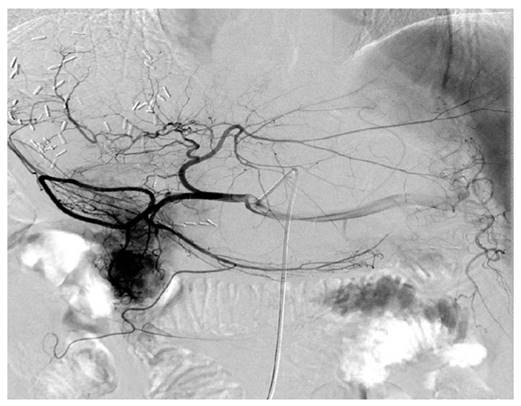

Figure 1

The representative digital subtraction angiography of the patients with HBV-associated ICC who received TACE. All patients who received postoperative TACE were due to early local recurrence of the tumor and all these patients demonstrated relatively abundant blood supply of tumor compared with others that the blood supply to the tumor was less abundant.

TACE was performed by an injection containing a mixture of chemotherapeutic agents with lipiodol followed by embolization with polyvinyl alcohol or gelatin foam up to complete stasis was attained in the tumor-feeding vessels. For the chemotherapeutic agents, epirubicin, cisplatin, and fluorouracil were concurrently used. All patients who received postoperative TACE were due to early recurrence of the tumor (Figure 1).

TACE was performed in 9 patients who demonstrated early recurrence of the tumor; the definition for the early recurrence included both detection of recurrence nodules in CT scans (n = 3) and elevation of serum CA19-9 levels (n = 6) within 12 months after surgery. All patients who received postoperative TACE were seropositive for HBsAg and HBcAb (Table 2). Among them, 4 patients demonstrated elevation of AFP and serum level of CA19-9 elevated in 5 patients. A total of 2 and 3 patients presented with lymph node metastasis and vascular invasion at the time of hepatic resection, respectively. Median size of the tumors was 9 cm (range, 2.5 to 16). All patients who received postoperative TACE demonstrated hepatic APE in preoperative CT scans.